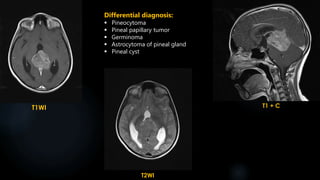

FLAIR

T1 + C

T1WI

T2WI

Differential diagnosis:

 Pineal cyst

 Pineoblastoma

 Pineal papillary tumor

 Germinoma

 Teratoma

 Astrocytoma of pineal gland